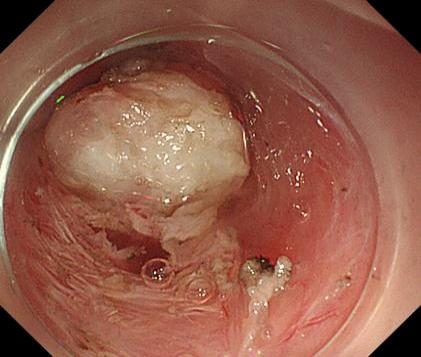

50f14f57e31f4fcb8cc67db07e7637a3.Jpeg5a155f6b9d364f049bf504276762fa4e.Jpegae69de3d0b564c66bdf2294699da75a6.Jpeg

胃底間質瘤                內鏡下全層切除術后創面         切除后標本

內鏡下全層切除術(EFTR):治療消化道黏膜下腫瘤(最主要):起源于固有肌層深層、部分腔外生長、與漿膜層密不可分;少部分抬舉征陰性消化道癌前病變和早期癌;少部分困難解剖部位結腸病變(如結腸憩室內腺瘤)等。